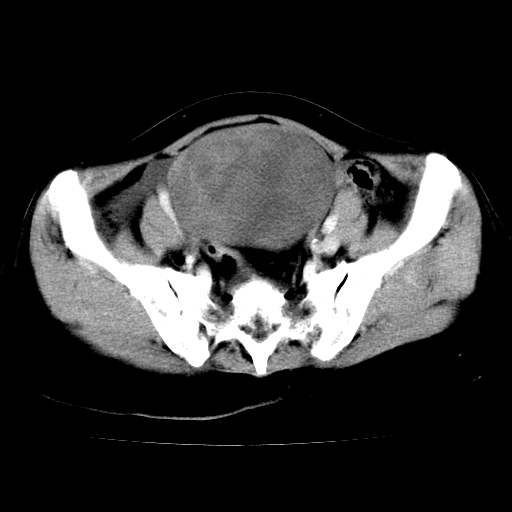

标题: CT24785:女,62岁,发现下腹部肿物半年。 [打印本页]

标题: CT24785:女,62岁,发现下腹部肿物半年。

女,62岁,发现下腹部肿物半年,下腹部不适。

支持卵巢癌

卵巢囊腺瘤或囊腺癌,建议免疫组化实验

卵巢囊腺瘤或囊腺癌可能。